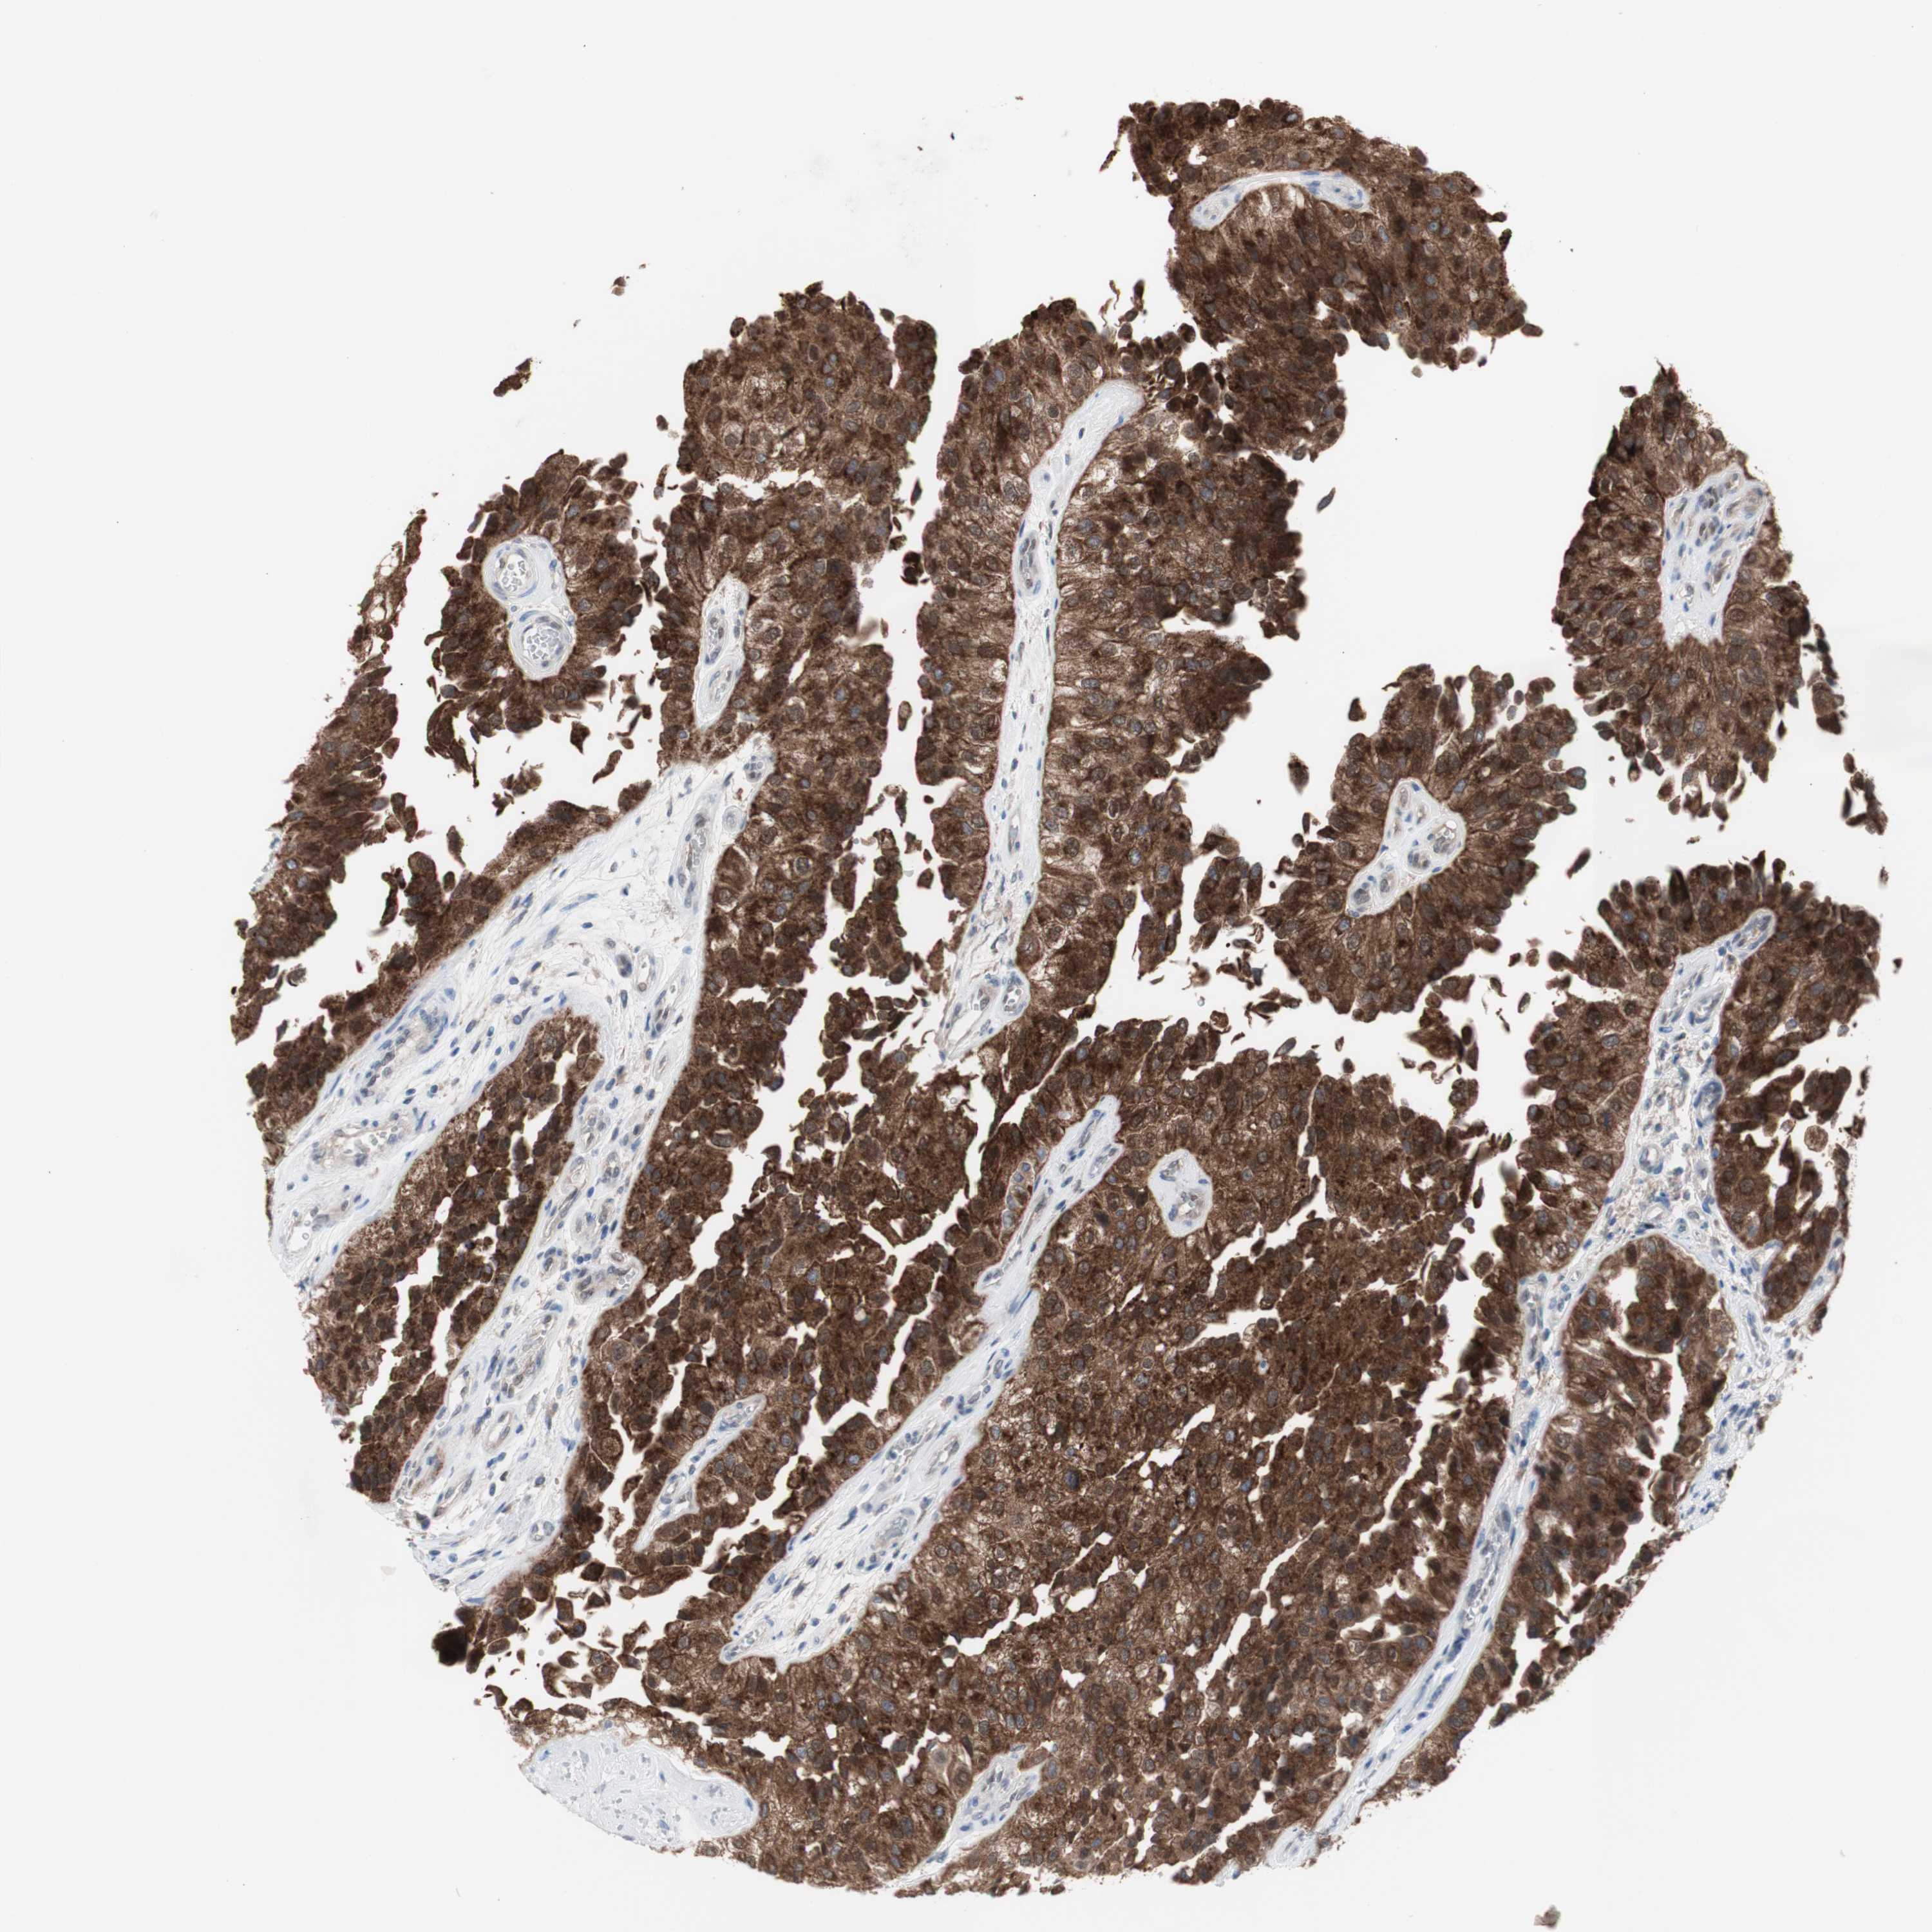

UROTHELIAL CANCER - Protein expressioni

A mouse-over function shows sample information and annotation data. Click on an image to view it in a full screen mode. Samples can be filtered based on level of antibody staining by selecting one or several of the following categories: high, medium, low and not detected. The assay and annotation is described here.

Note that samples used for immunohistochemistry by the Human Protein Atlas do not correspond to samples in the TCGA dataset.

Antibody stainingi

Antibody staining in the annotated cell types in the current human tissue is reported as not detected, low, medium, or high, based on conventional immunohistochemistry profiling in selected tissues. This score is based on the combination of the staining intensity and fraction of stained cells.

Each image is clickable and will lead to virtual microscopy that enables deeper exploration of all samples and also displays staining intensity scores, fraction scores and subcellular localization as well as patient and tissue information for each sample.

Antibody HPA005525

Antibody HPA064708

Antibody CAB012459

Staining

High

Medium

Low

Not detected

Intensity

Strong

Moderate

Weak

Negative

Quantity

>75%

75%-25%

<25%

None

Location

Nuclear

Cytoplasmic/membranous

Cytoplasmic/membranous,nuclear

Urothelial carcinoma, High grade